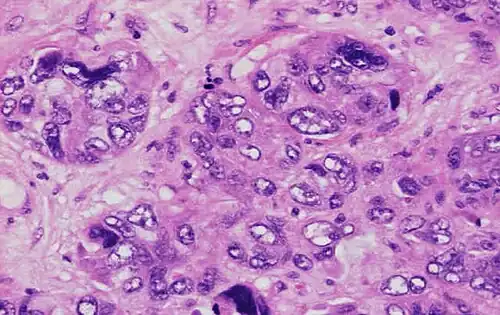

Nuclear pleomorphism

This parameter assesses whether the cell nuclei are uniform like those in normal breast duct epithelial cells, or whether they are larger, darker, or irregular (pleomorphic). In cancer, the mechanisms that control genes and chromosomes in the nucleus break down, and irregular nuclei and pleomorphic changes are signs of abnormal cell reproduction.

Note: The cancer areas having cells with the greatest cellular abnormalities should be evaluated.

- 3 points: nuclei with marked variation in size and shape

Invasive ductal carcinoma with marked nuclear pleomorphism.